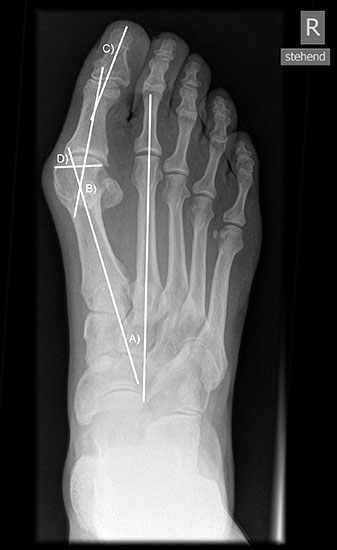

Präoperatives Röntgenbild Fuß d.p. mit eingezeichneten Winkeln. A) Intermetatarsalwinkel, B) Hallux valgus Winkel, C) Interphalangeal-Winkel.

Abbildung 2

• Operationsplanung anhand der Röntgenaufnahmen unter Beachtung wichtiger radiologischer Landmarks wie Intermetatarsalwinkel, Hallux valgus – Winkel, distaler Gelenkflächenwinkel (Distal Metatarsal Articular Angulation - DMAA), Metatarsaleindex und Sesambeinposition (Abb. 2).